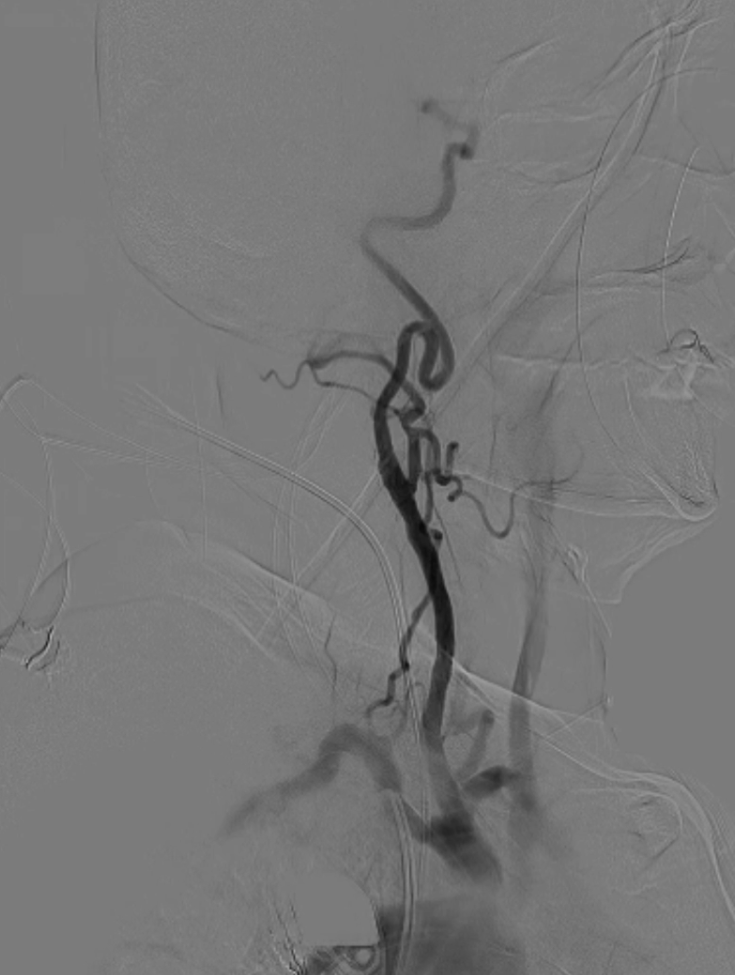

导丝与导管操作:超滑导丝配合多用途导管选入无名动脉,调整角度进入右锁骨下动脉;因主动脉弓扭曲严重,更换支撑导管通过病变段并造影证实

超选入无名动脉

无名动脉起始支架内

重度狭窄

脑保护措施:更换加硬导丝后,采用Filterwire保护伞及0.018导丝选入右颈总动脉,进一步送入右颈内动脉释放保护伞。

跟进长鞘至无名动脉起始

Filterwire 3.5-5.5 保护伞

导丝选入右颈总动脉内

导丝选入右颈内动脉

放置保护伞